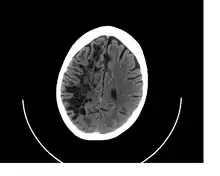

A perivascular space as seen on CT | |

Perivascular spaces are distinguished on an MRI by several key features. The spaces appear as distinct round or oval entities with a signal intensity visually equivalent to that of cerebrospinal fluid in the subarachnoid space.[7][14][15] In addition, a perivascular space has no mass effect and is located along the blood vessel around which it forms.[14]